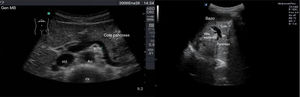

Con el transductor convexo, en epigastrio, realizaremos cortes transversales, longitudinales y oblicuos. Con la sonda en disposición transversal a nivel de epigastrio conseguimos un corte longitudinal del páncreas (fig. 9). Ventralmente o en superficie al páncreas nos encontramos con el lóbulo hepático izquierdo haciendo de ventana acústica. Dorsalmente o en profundidad con respecto al páncreas se sitúan la confluencia esplenoportal, la vena esplénica, la arteria mesentérica superior y la aorta, entre las que discurre la vena renal izquierda que desemboca en la cava.

Con la sonda en disposición longitudinal a nivel de epigastrio conseguimos un corte transversal del páncreas (fig. 10). Ventralmente o en superficie al páncreas nos encontramos con el lóbulo hepático izquierdo y el estómago con contenido líquido. Dorsalmente o en profundidad con respecto al páncreas se sitúan la arteria mesentérica superior y la aorta, entre las que discurre la vena renal izquierda.

El corte oblicuo a nivel del epigastrio se usa para la visualización de la cola del páncreas y consiste en situar la sonda de manera oblicua apuntando hacia el hombro izquierdo del paciente. La cola del páncreas también se puede visualizar, en ocasiones, con cortes a nivel de flanco izquierdo utilizando el bazo como ventana acústica (fig. 11).

A la izquierda, imagen de la cola del páncreas conseguida con la sonda en disposición oblicua a nivel de epigastrio apuntando hacia el hombro izquierdo del paciente, con la arteria mesentérica superior (ams), aorta (Ao), vena cava inferior (VCI) y cuerpo vertebral (CV). A la derecha, visualización de la cola del páncreas a través de la ventana del bazo.